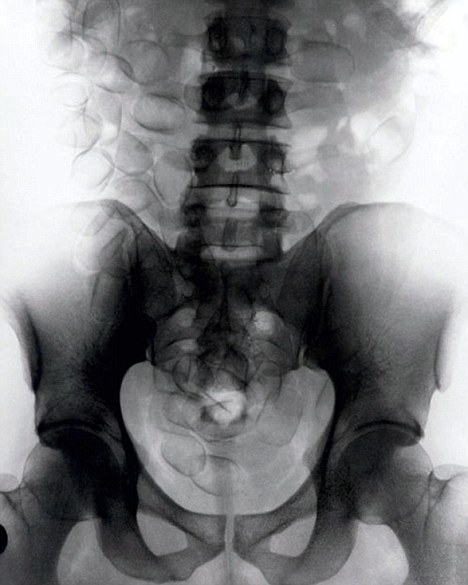

現(xiàn)年30歲的菲達利斯(Fidelis Ozouli)冒著生命危險將重達1公斤的毒品吞下,被抓后卻辯稱不知道吞下的是毒品。當時,曼徹斯特機場的海關人員看到毒販菲達利斯臃腫的肚腩,顯得很不自然,于是開始懷疑。檢查人員用X射線機照他的胃部時,發(fā)現(xiàn)了大量可卡因。目前他已被送往附近醫(yī)院,以確保排出所有的毒品。